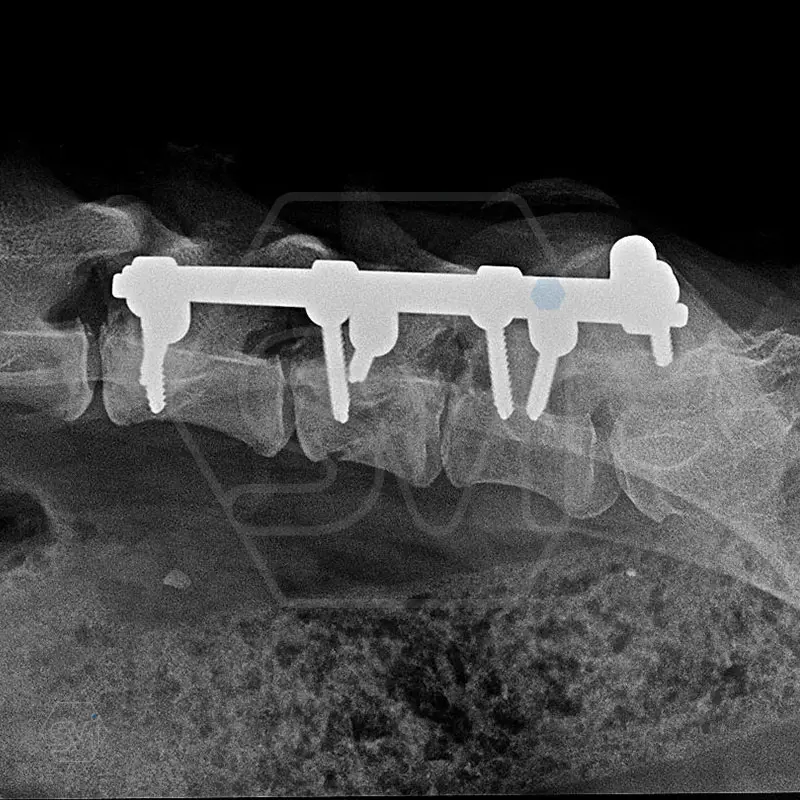

L6 vertebral body fracture fixation with 2.7-mm SOP-LC system

We performed a laminectomy of L7 and then performed fixation with a 4-4 clamp, bilateral 2.7-mm SOP-LC system. Control x-rays were taken at 6 and 12 weeks after surgery. Based on the video, in our opinion, the dog has recovered… :)